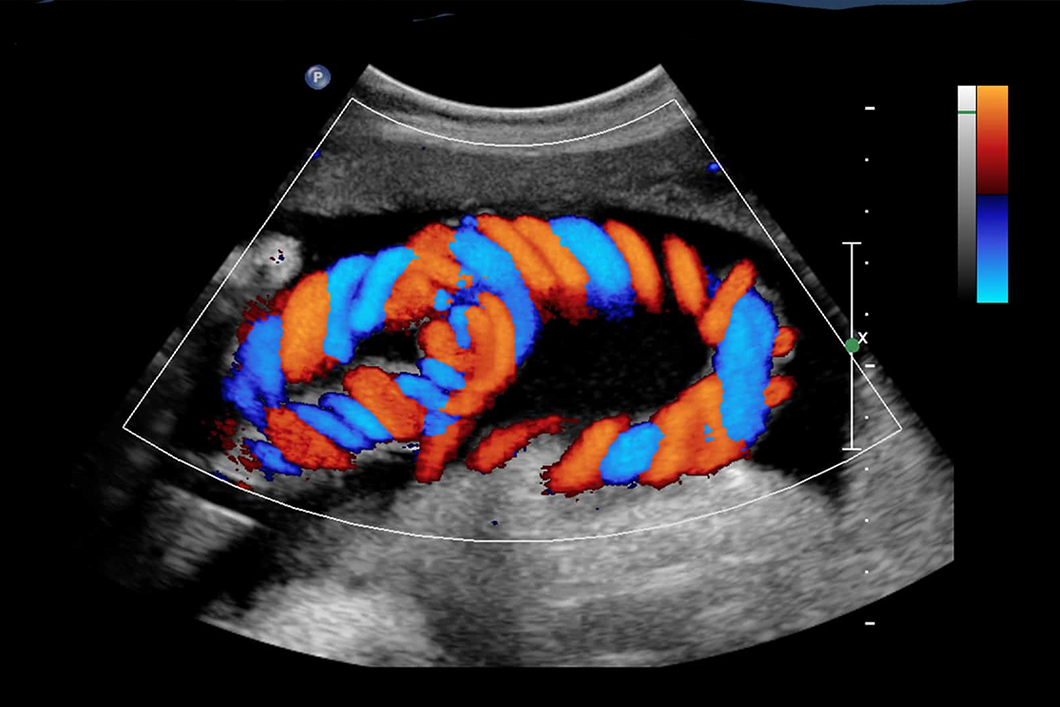

Colour Doppler

Detailed blood flow analysis for vascular and cardiac conditions.